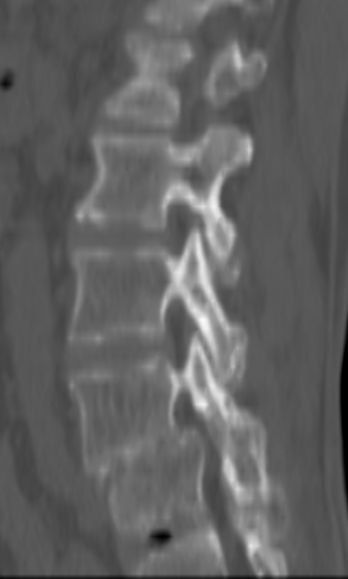

以下是引用余辉在2007-9-4 21:00:00的发言:[br]椎体棘突有点异常(像是被切割了),不知有否手术史,如椎体融合术等。单纯的退行性变可以出现椎间隙变窄,但同时一般会出现椎体上下缘的硬化增生,且椎体间完全融合的机率更小,本例椎体完全融合且椎体上下皮质缘破坏掉了,如果没有手术史,就应该考虑椎间盘炎性病变了,且椎体棘突及棘间韧带的变化也并不是不支持这个,多数小关节也融合了,且其形态也容易让人联想到如强脊炎及类风关等病变。[br][br][本贴已被 余辉 于 2007-9-4 21:03:55 修改过]

以下是引用chry3在2007-9-4 20:42:00的发言:[br]椎间盘病史?是什么样的病史,无双下肢放射痛,那就不是椎间盘突出了。是感染、什么性质的?[br]从图象看椎间隙消失,椎间盘组织未见,锥体滑脱是因为椎间盘溶解造成的[br]l4、5椎体骨质结构未见异常,l5上缘是l4的长期压迫所致[br]还是考虑椎间盘感染,结核。[br]